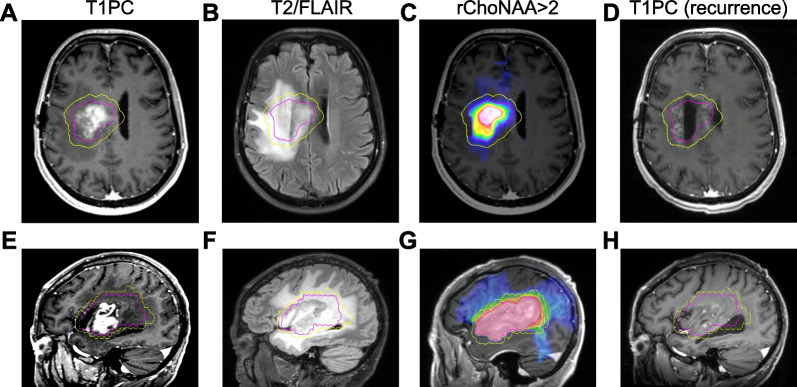

Of the 14 patients scanned, 11 received re-RT. Reasons for not proceeding with re-RT were rapid performance status decline and hospice (n = 2) or patient preference for systemic therapy (n = 1). For these 11 patients, median follow-up was 8.0 months (range 4.9–16.3 months). Out of the 11 patients, 8 failed in-field. Three out of the eight in-field failures were outside the T1PC delineated GTV, but within the rChoNAA > 2 delineated GTV (Fig. 4). Median survival time was 7.1 months and median progression-free survival was 6.5 months (Fig. 5). No grade 3 or higher toxicity were observed that were probably or definitely related to RT.

Fig. 4.

Two patients with recurrence within rChoNAA > 2 but outside of T1 post-contrast delineated GTV. A Axial pre-treatment T1PC from patient with rGBM treated with re-RT. Yellow outlines the CTV and magenta contour outlines the pre-treatment rChoNAA > 2 volume. B Pre-treatment T2/FLAIR. C rChoNAA > 2 overlaid pre-treatment T1PC. D Post-treatment T1PC. An area of recurrence is seen medially that was identified by the initial rChoNAA > 2 maps. E Sagittal pre-treatment T1PC from a separate patient with rGBM treated with re-RT. Yellow outlines the CTV and magenta contour outlines the pre-treatment rChoNAA > 2 volume. F Pre-treatment T2/FLAIR. G rChoNAA > 2 overlaid pre-treatment T1PC. H Post-treatment T1PC. Area of recurrence posteriorly was largely included in the rChoNAA > 2 volume but not T1PC volume. Note that areas of recurrence are not avidly enhancing due to concurrent bevacizumab administration